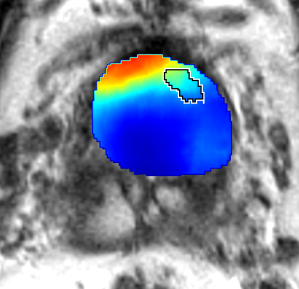

Qualitative Evaluation: Figure 4 shows the same slice as in Figure 2 with aligned T2W, ADC, and histopathology images, and prediction results using current state-of-the-art method [4], our CorrSigNet() and CorrSigNet(T2W, ADC, ) models. It may be noted that [4] fails to detect the cancerous regions on the left and right of the images, while the CorrNet representations alone can identify the cancer regions, and when combined with T2W and ADC images, they predict the cancer regions with high probability. It may also be noted that CorrSigNet(T2W, ADC, ) shows fewer false positives than [4]. This example shows the strength of learning correlated MRI signatures in identifying subtle, and sometimes MRI-invisible cancers. Figure 5 shows more example slices from different patients, comparing the state-of-the-art approach [4] and our prediction results with CorrSigNet(T2W, ADC, ). We note that our model with correlated features (1) can identify subtle and smaller cancer regions, (2) have better overlap with ground truth cancer labels, and (3) have fewer false positives.